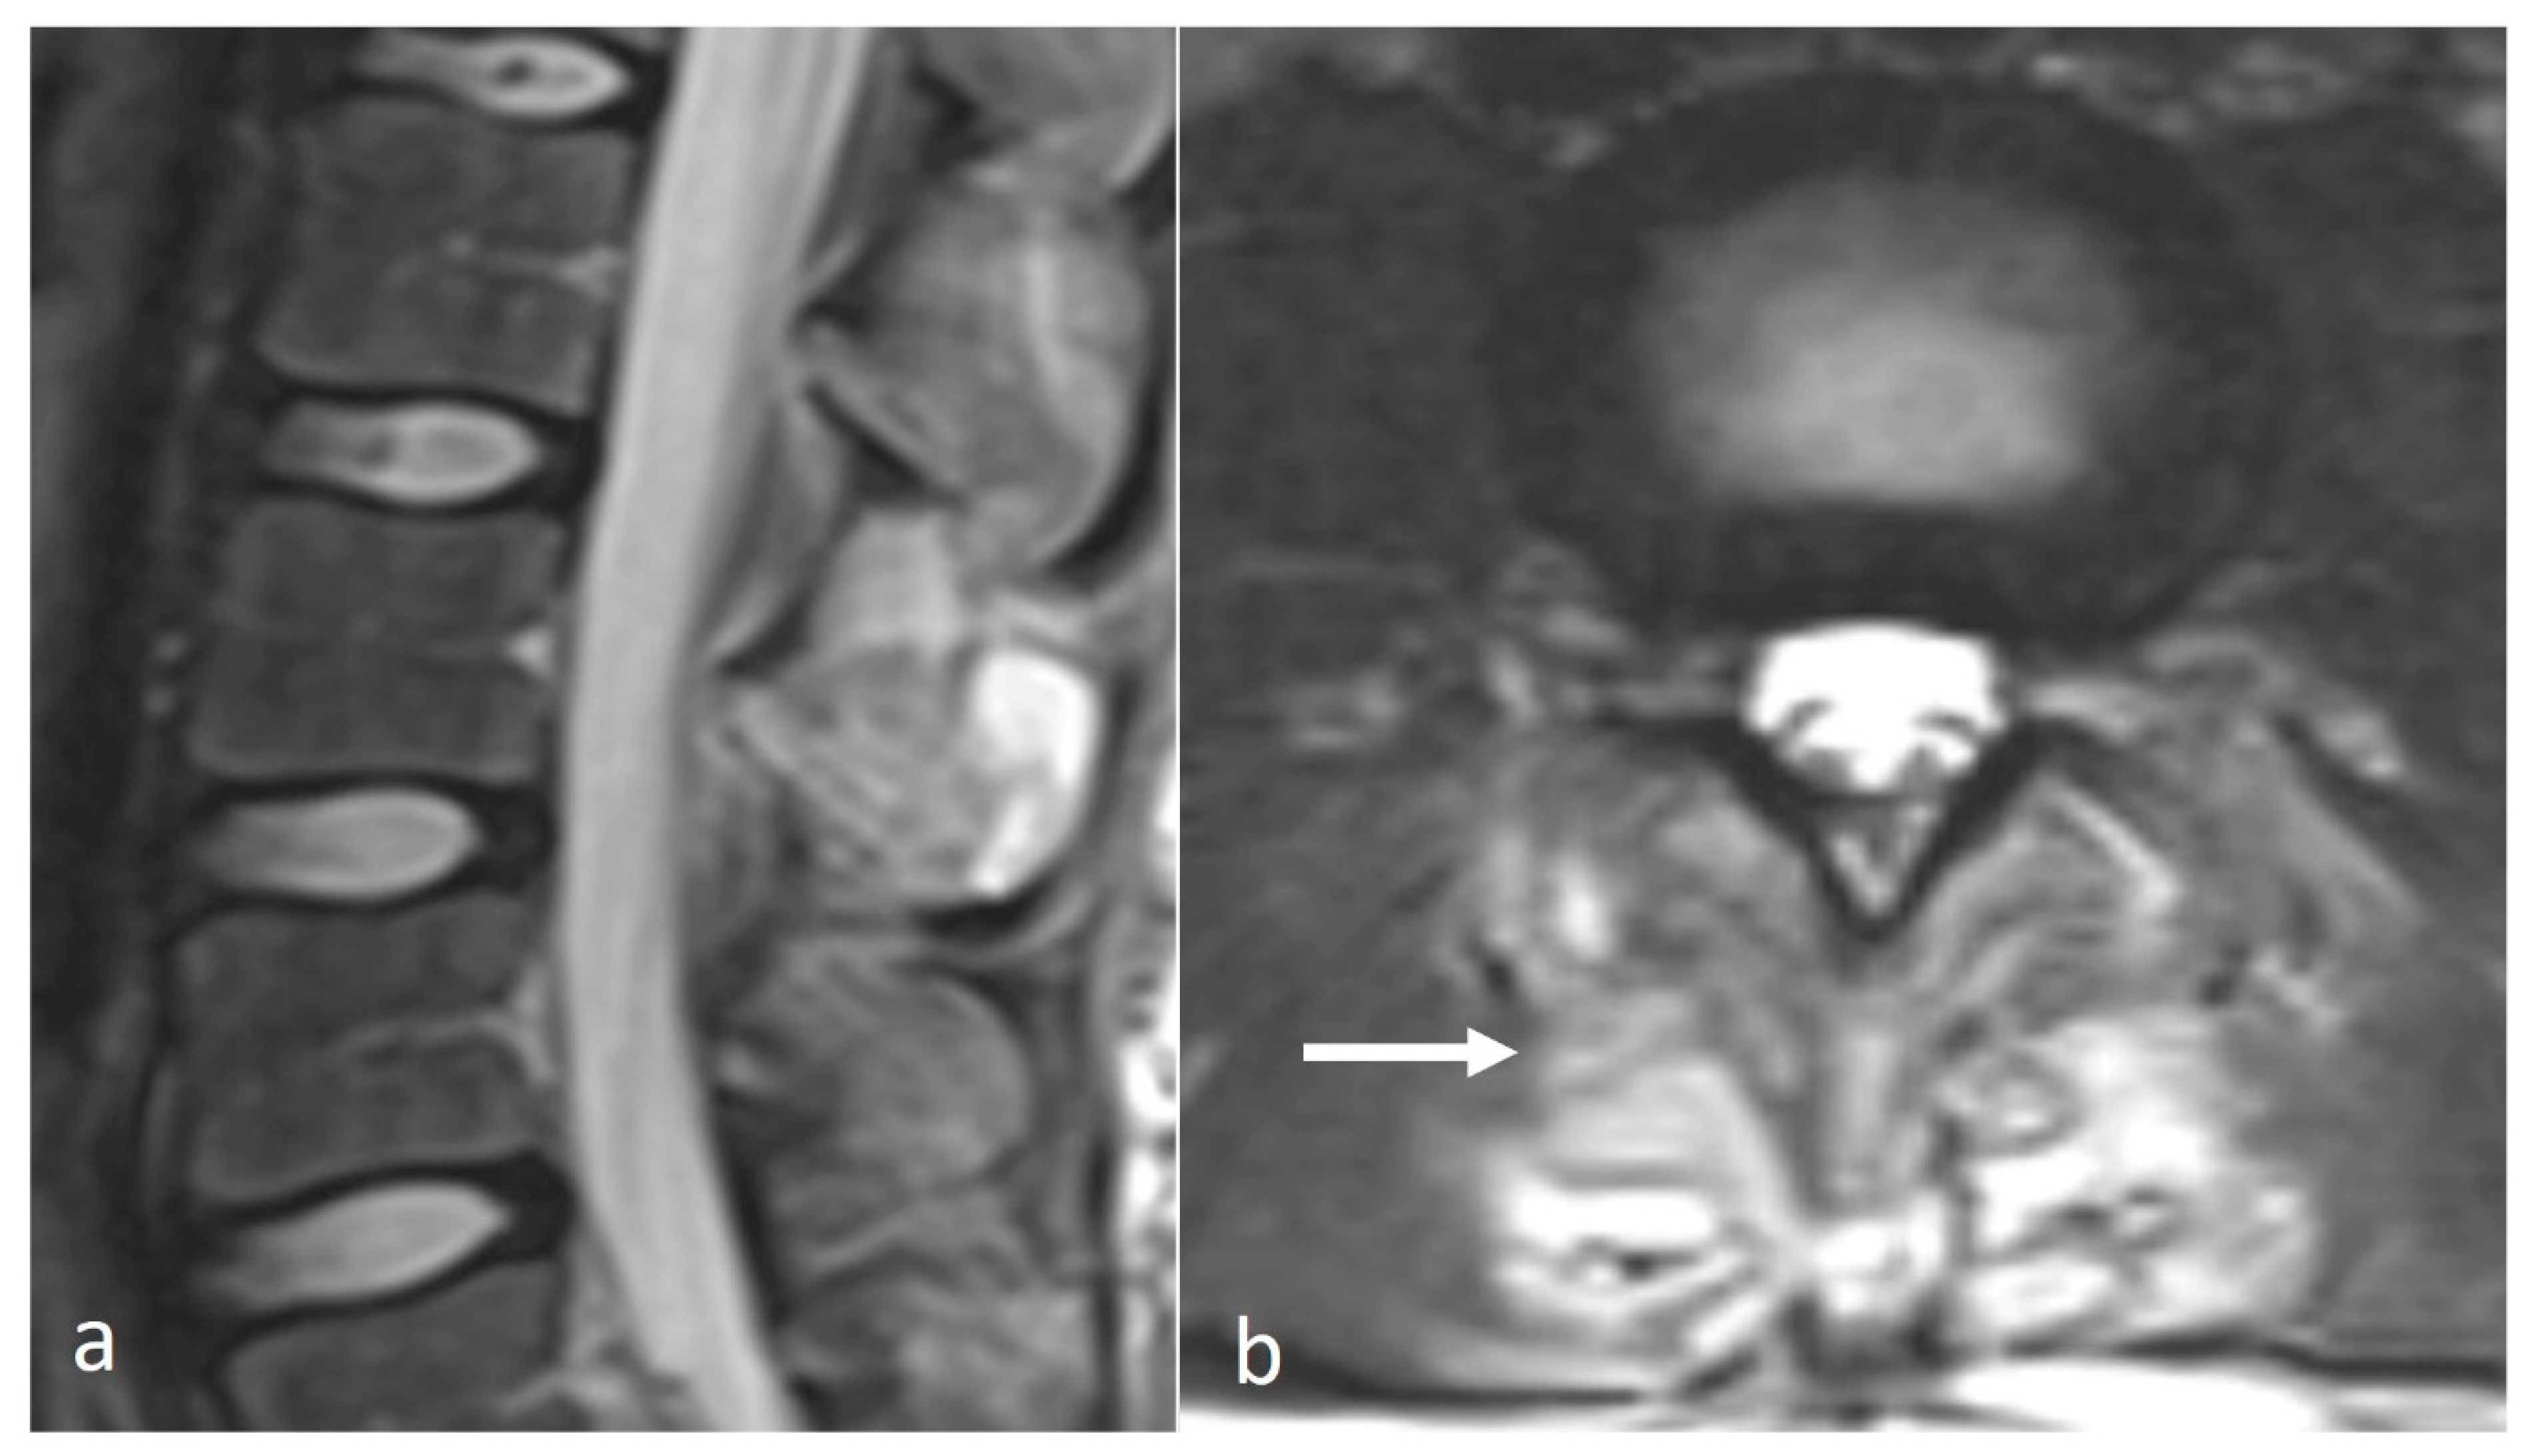

3.3.4. Aneurysmal Bone Cyst (ABC)

ABCs are benign locally aggressive lesions, with a predilection for the posterior spinal elements [15,18]. The lesions tend to be lytic and expansile. Thin bony septa may be present within the lesion, best appreciated on CT. MRI will show a cystic lesion with high signal on fluid-sensitive sequences, and the typical fluid–fluid levels. (Figure 4a–c) Rarely, solid components may also be present. These components as well as the septa can enhance.

Figure 4.

Sagittal T2 (a), axial T2 (b) and axial CT (c) images demonstrating an aneurysmal bone cyst of a cervical spinous process (white arrows). Note the lytic osseous destruction on CT and the characteristic presence of fluid–fluid levels on MRI.

It is important to distinguish primary ABCs from secondary ABC change occurring in association with other lesions such as fibrous dysplasia, GCT and even osteosarcoma, and the rare telangiectatic osteosarcoma, although osteosarcomas isolated to the spinous process are rare [3].